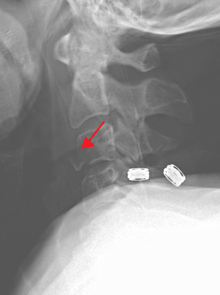

Severe pain will usually be present at the point of injury. Pressure on a nerve may also cause pain from the neck down the shoulders and/or arms. Bruising and swelling may be present at the back of the neck. A neurological exam will be performed to assess for spinal cord injury. X-rays will be ordered to determine the severity and location of the fracture. CT (computed tomography) scans may be ordered to assess for gross abnormalities not visible by regular X-ray. MRI (magnetic resonance imaging) tests may be ordered to provide high resolution images of soft tissue and determine whether there has been damage to the spinal cord, although such damage is usually obvious in the conscious patient because of the immediate functional consequences of numbness and paralysis in much of the body.

It is also common for imaging (either a plain film X-ray or CT scan) to be completed when assessing a cervical injury. This is the most common way to diagnose the location and severity of the fracture. To decrease the use C-spine scans yielding negative findings for fracture, thus unnecessarily exposing people to radiation and increase time in the hospital and cost of the visit, multiple clinical decision support rules have been developed to help clinicians weigh the option to scan a patient with a neck injury. Among these are the Canadian C-spine rule[1] and the NEXUS criteria for C-Spine imaging,[2] which both help make these decisions from easily obtained information. Both rules are widely used in emergency departments and by paramedics.